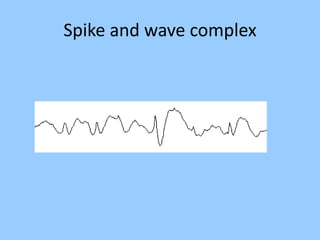

1. The document discusses EEG patterns and findings in various neurological conditions seen in children. It includes descriptions of normal EEG findings as well as abnormal patterns seen in conditions like absence seizures, West syndrome, benign childhood epilepsy with centrotemporal spikes, Lennox-Gastaut syndrome, non-convulsive status epilepticus, subacute sclerosing panencephalitis, and herpes encephalitis.

3. International standards for EEG electrode placement and recording parameters are reviewed. Characteristics of different EEG waves, amplitudes, and patterns are described.